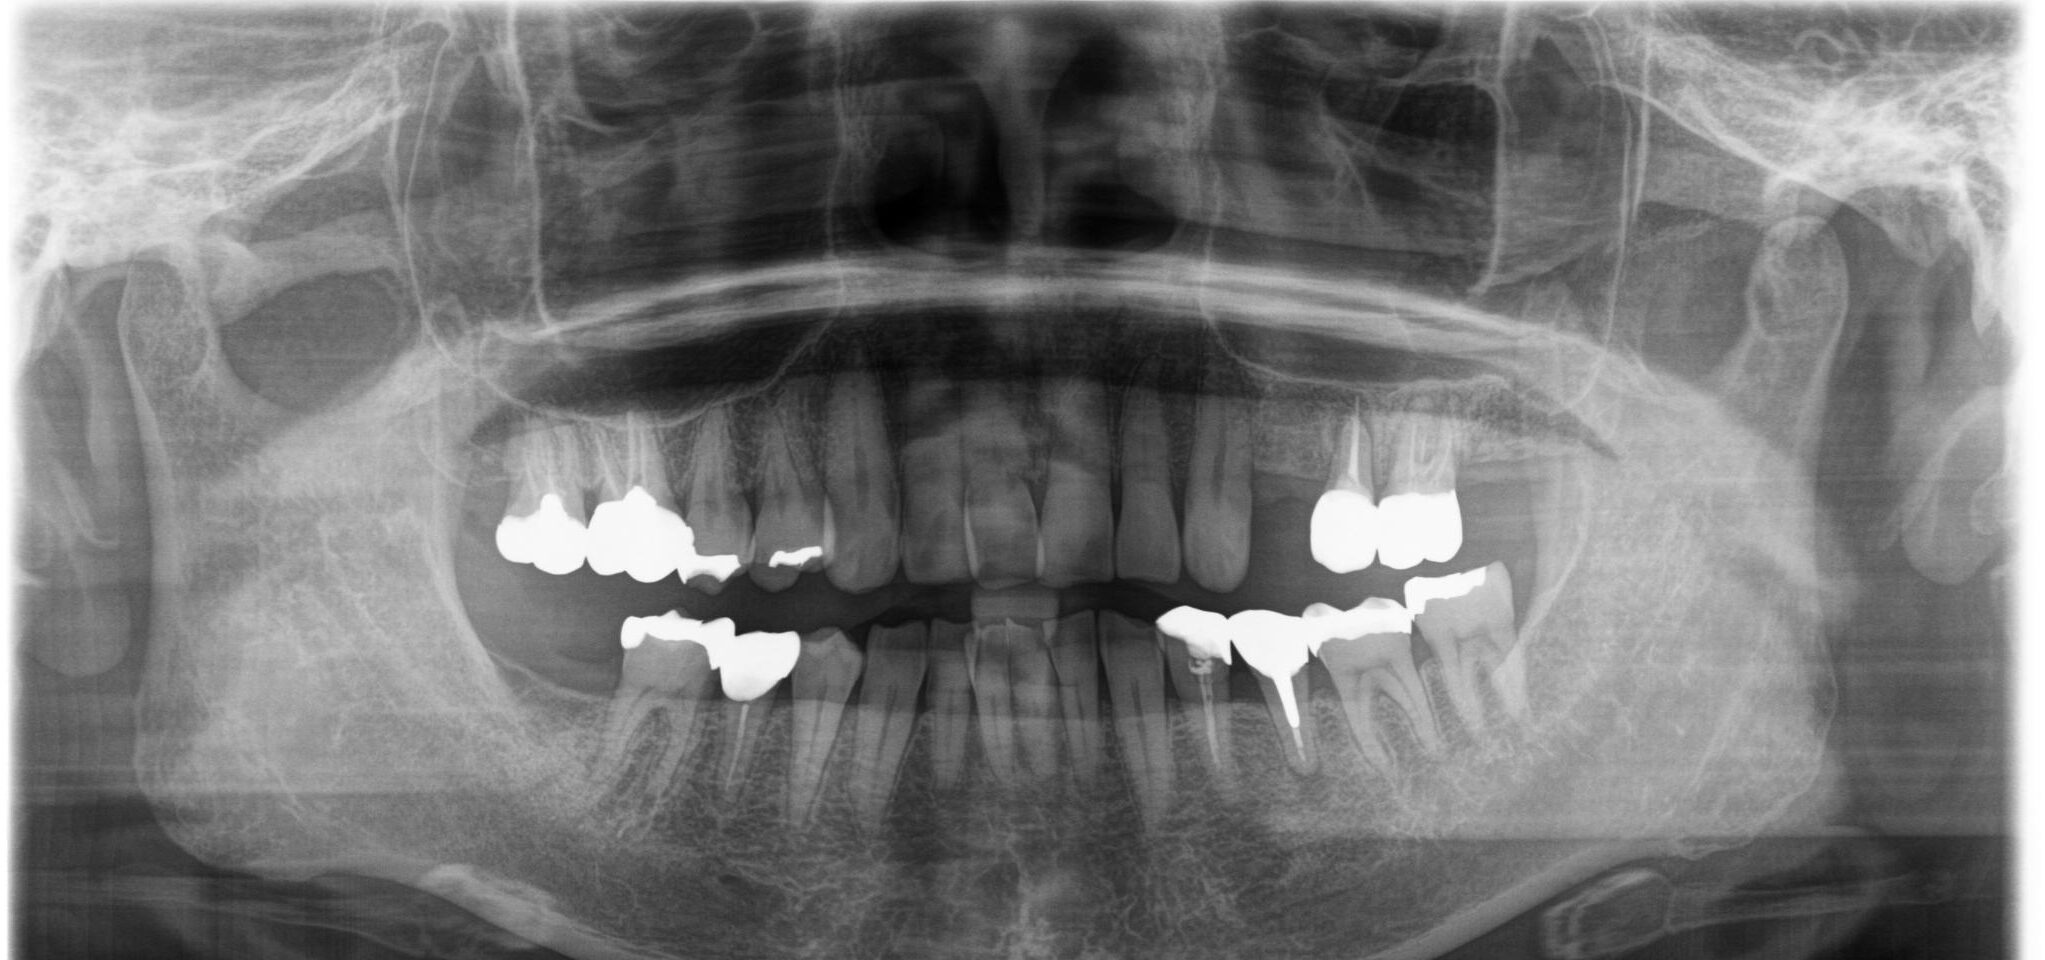

治療前レントゲン画像